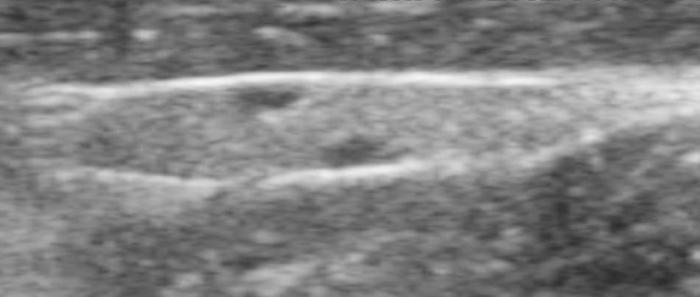

Relación entre el diámetro tiroideo (TD) y el diámetro de la arteria carótida común (CCA)

El uso de estructuras vasculares adyacentes como referencias anatómicas ha sido una estrategia útil en ecografía veterinaria para estandarizar las mediciones de órganos pequeños como la glándula tiroides. En este contexto, Bandula Kumara et al. (2019) propusieron la medición de la relación entre el diámetro tiroideo (TD) y el diámetro de la arteria carótida común (CCA) como una forma práctica de evaluar el tamaño de la glándula en perros clínicamente normales (Figura 5A-B).

Los autores realizaron un estudio en el que midieron el diámetro anteroposterior de los lóbulos tiroideos y el diámetro externo de la CCA en cortes transversales obtenidos a nivel del cuello medio. Encontraron que esta relación se mantiene relativamente constante entre razas y tamaños corporales, sugiriendo que puede ser utilizada como parámetro de referencia ecográfica. Específicamente, en perros adultos sanos, la relación TD/CCA fue de 1.74 ± 0.40 (rango 1.11–2.43)6. Si los valores se encuentran por debajo del rango normal pueden ser considerados potencialmente indicativos de hipoplasia tiroidea o atrofia glandular.

Una ventaja de esta relación es que la arteria carótida común es fácilmente identificable ecográficamente, presenta un diámetro estable y poco variable en condiciones fisiológicas, y se ubica en estrecha proximidad con la glándula tiroides. Esto la convierte en una excelente estructura de referencia para normalizar mediciones entre individuos de diferente tamaño corporal, permitiendo evaluaciones objetivas en poblaciones mixtas de perros de compañía.

Además, este índice podría tener aplicación clínica en el seguimiento de animales con enfermedad tiroidea subclínica o en tratamiento, ya que permite detectar cambios discretos en el volumen glandular con buena reproducibilidad interobservador. Aunque su utilidad clínica requiere aún validación en animales con patología confirmada, representa una herramienta complementaria valiosa dentro del enfoque ecográfico sistemático de la glándula tiroides en pequeños animales.